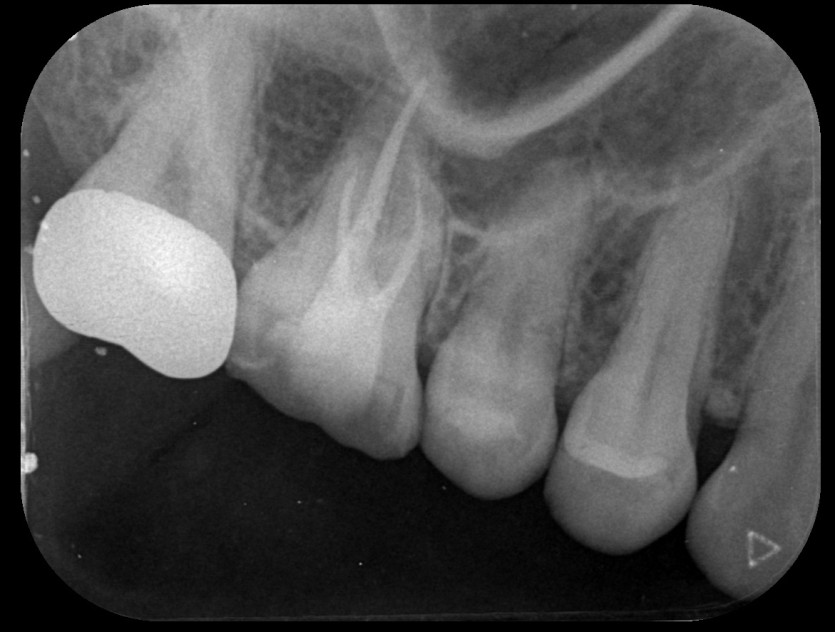

임플란트 사례